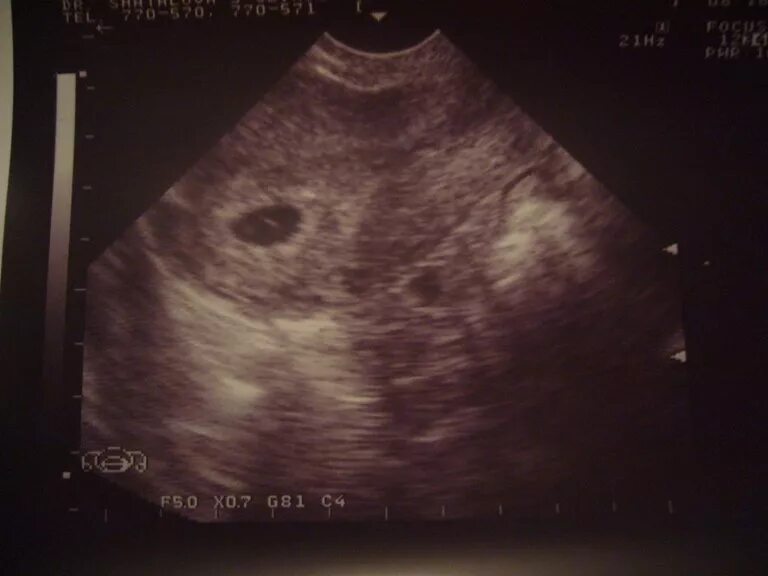

Желточный мешок 2 мм